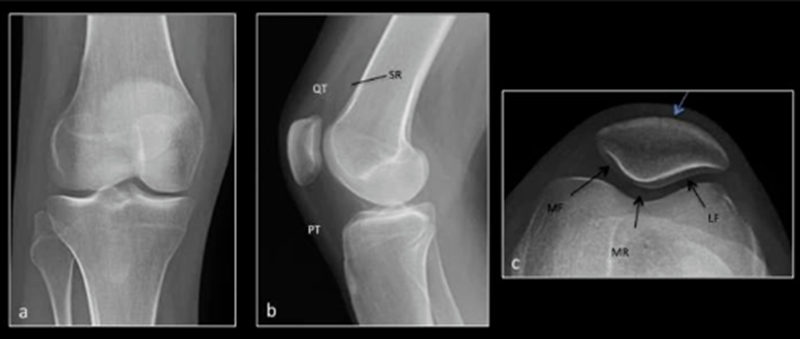

常见影像学检查包括X线、CT和MRI检查。X线早期无异常,直到晚期阶段,如出现广泛的软骨丧失、关节间隙丧失及相关的软骨下骨硬化和囊性变化,X线可诊断。MRI是非侵入性诊断方法,有望在肉眼可见的形态学软骨损失之前检测软骨病变以及软骨内部紊乱的独特功能。

正常X线 a.膝关节正位 b.膝关节侧位 c.髌骨轴位

髌骨软骨软化平片及CT表现:膝关节侧位片示关节间隙变窄, 关节缘皮质线有中断。CT示髌股关节略有错位,关节间隙变窄,软骨下骨质密度增高